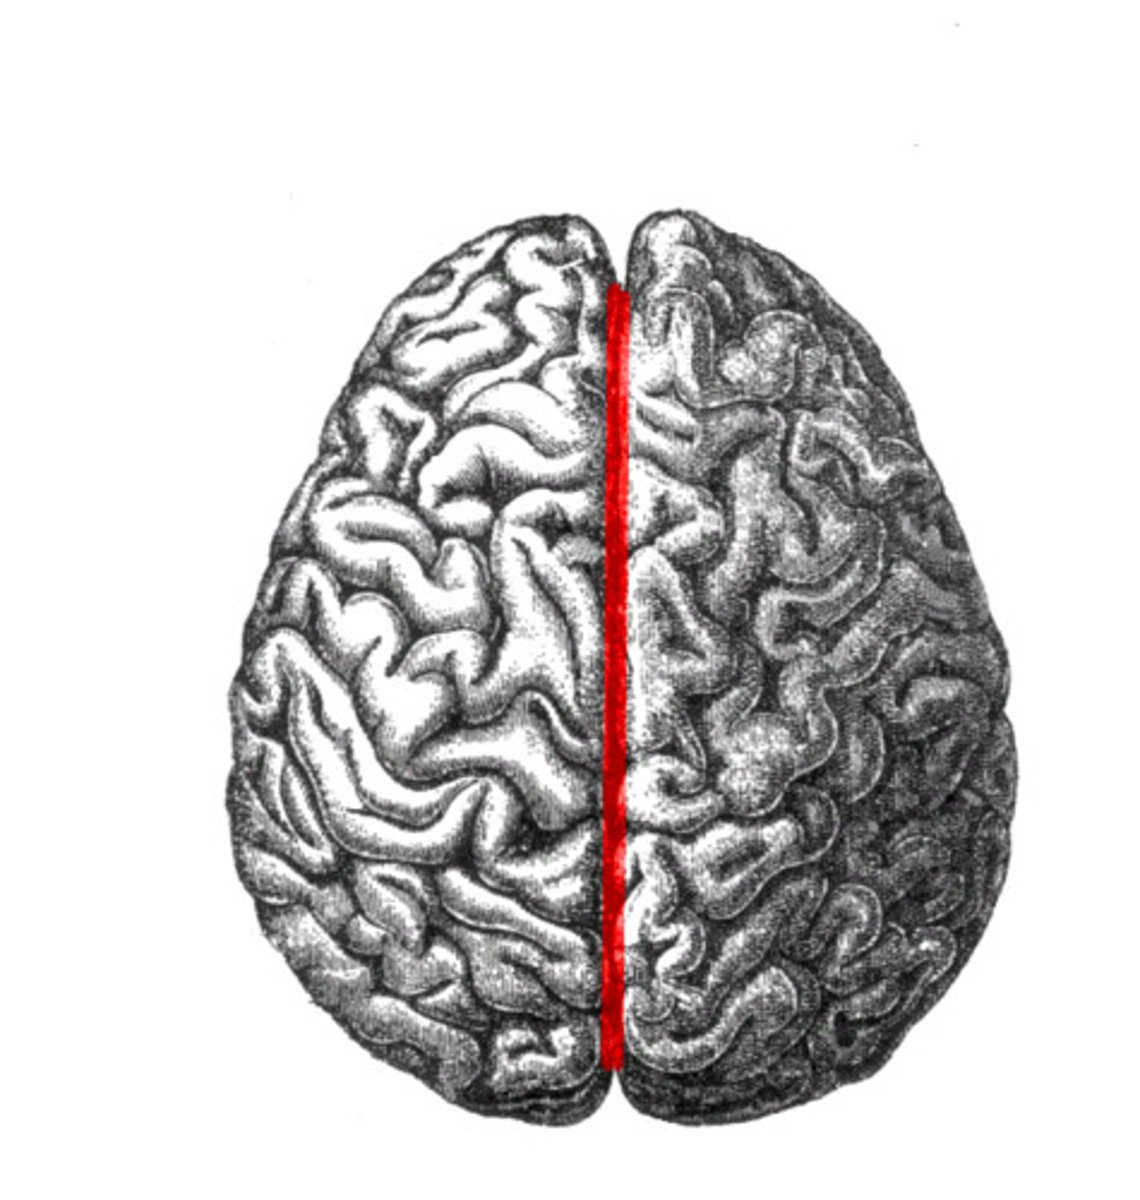

longitudinal fissure